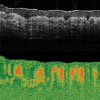

Figure 116W Speckle variance measurement showing blood vessels of a mouse brain.

Speckle Variance Mode

The speckle variance imaging mode is an acquisition mode which uses the variance of speckle noise to calculate angiographic images. It can be used to visualize three dimensional vessel trees without requiring significant blood flow and without requiring a specific acquisition speed window. The speckle variance data can be overlaid on top of intensity pictures providing morphological information. Different color maps can be used to display the multimodal pictures.